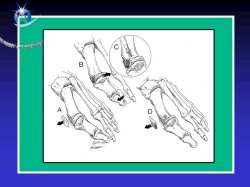

L’ostéotomie « SCARF »

Le « SCARF » est une technique fréquemment employée. Une fois l’exostose retirée, une ostéotomie est réalisée sur le métatarsien du gros orteil. Le chirurgien fait glisser les deux fragments osseux l’un sur l’autre et les fixe avec des vis.

Le chevron

Le chirurgien discutera avec vous de la technique la mieux adaptée à votre cas en fonction de différents critères (âge, activités…). Ces différents traitement chirurgicaux peuvent corriger l’hallux valgus mais une seconde ostéotomie est fréquemment pratiquée dans la phalange pour redresser le gros orteil.

Le traitement consiste en une ostéotomie des autres métatarsiens (ostéotomie de Weil). Ce geste fait reculer la tête métatarsienne ce qui a pour effet de décomprimer l’articulation. Les ostéotomies de Weil sont généralement fixées par une vis.